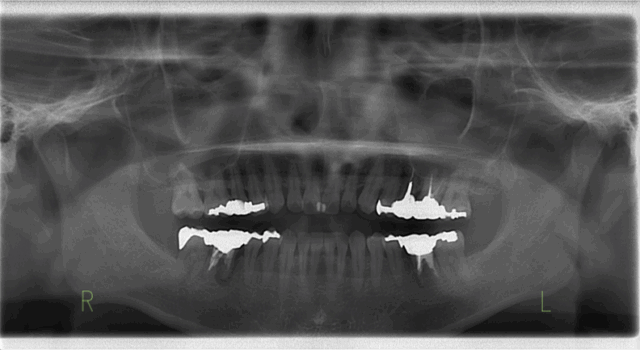

Before

After

| 通院時の年齢 | 55歳 |

|---|---|

| 性別 | 女性 |

| 通院回数 | 約1年 |

| 通院目的 | 見た目をきれいにしたい |

| 処置内容 | 下顎臼歯部欠損→インプラント 下顎前歯部根尖性歯周炎→根管治療 既存の上下補綴物(セラミック冠)を撤去し、咬合(かみ合わせ)の再建や人口歯の形態の変更などのフルマウス治療 |

| 備考 | 【診断名】下顎臼歯部(奥歯)欠損、下顎前歯根尖性歯周炎 下顎前歯の根尖性歯周炎により病巣から膿が出ていたが、マイクロスコープを用いた根管治療を行うことにより、下顎前歯を残すことが可能となった。 |